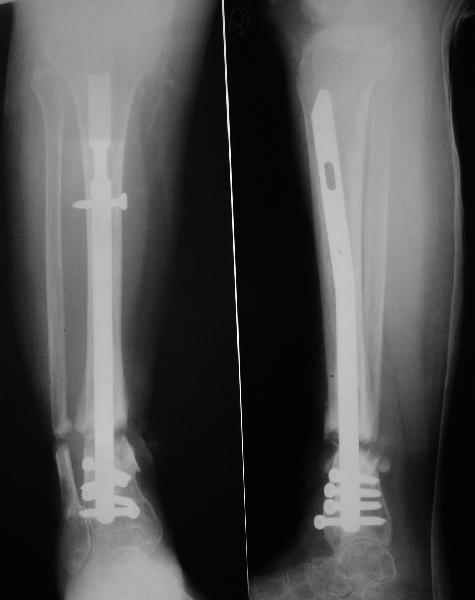

Аппарат - чтобы плавно исправить ось. В приложении - снимки на момент окончания коррекции в аппарате, фото с операции, и послеоперационная рентгенограмма.

Диаметр гвоздика 10,5 мм. Пришлось укорачивать до 23 см - уж очень миниатюрная дама, отверстия насверлил под 45 градусов, под 5 мм винты. По оси удалось сблизить до этого положения. Заперли гвоздь пока статически с планом через 2 месяца верхний винт убрать. Но это ей придется уже в Ташкенте сделать. Что скажете? Спасибо.

In attachment - x-rays at the end of alignment, the surgery, and result. The nail was cut to 23 cm. Four 45 degree holes were pre-drilled at the distal nail tip. The nail was locked statically

after some impaction. Dynamization is considered in 8 weeks. Any comments/critics?

NL> If you dynamise before regenerate maturation, d'ont you loose lenght?

Sure. Frankly speaking the target was just functional stable aligned limb regardless of shortening. I don't expect regenerate appearance, but what if i am wrong? If the bonus appears in the gap, we'll give it 2 month to mature. Anyway x-rays will be taken prior screw removal so dynamization can be postponed if necessary.